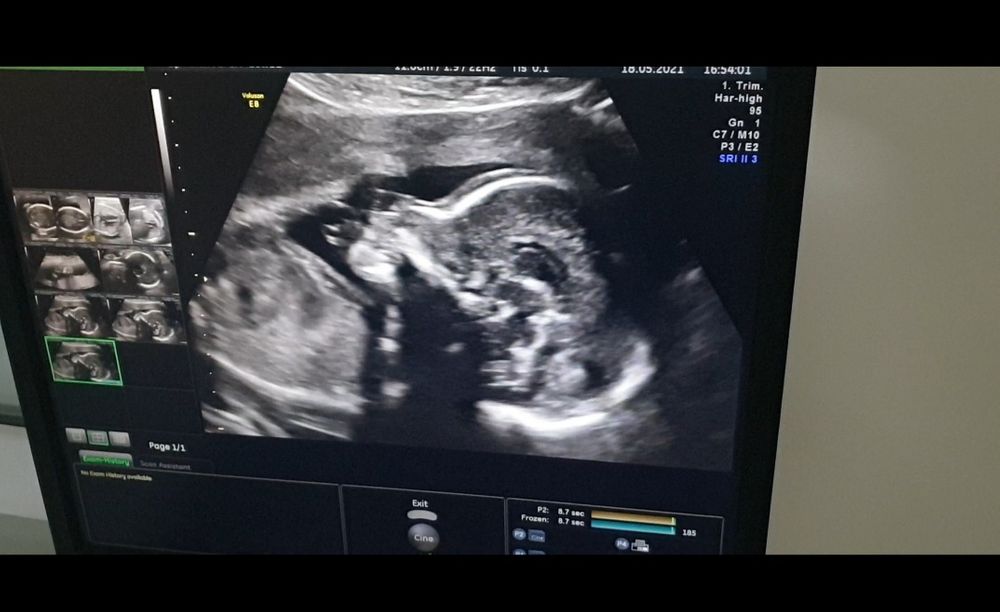

20+2нед. Дочка))

Ну что, сходила я сегодня на скрининг, всё у малышки хорошо, 340гр уже, растёт.))Пол совпал, сдавала в инвитро в 10+2 на выявление У хромосомы, хромосому не нашли...ждём вторую доченьку🥰